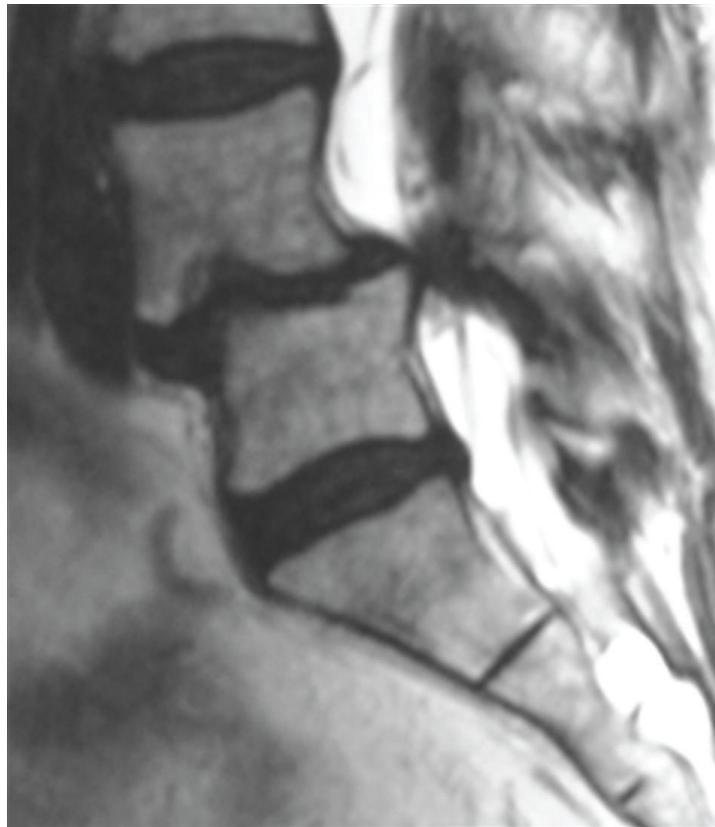

L5/S1 Disc Herniation Example:

Lumbar Disc Herniation

- Significance: Very common cause of low back pain and unilateral leg pain (radiculopathy)

- Diagnosis: Made clinically and confirmed with MRI studies of lumbar spine

- Initial treatment: Nonoperative with oral medications and physical therapy for radicular leg pain

- Surgical indication: Microdiscectomy for severe pain and/or motor deficit that have failed to respond to nonoperative management